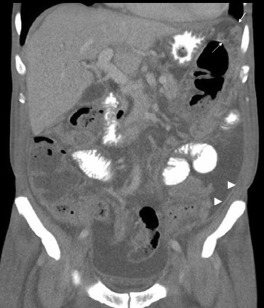

A 64-year-old man presented with abdominal fullness and intermittent night fever for 1 month. His medical history included hemodialysis for 1 year and hypertension. He did not drink alcohol and had no history of chronic hepatitis B or hepatitis C virus infection. There was no body weight loss, cough, or bowel habit change. His physical examination revealed abdominal distension and shifting dullness on percussion. Laboratory workup revealed anemia (hemoglobin, 8.4 g/dL) and hypoalbuminemia (albumin, 2.8 g/dL). The chest radiograph was normal. An abdominal computed tomography with contrast showed ascites, smooth uniform thickening of the peritoneum (arrowhead), omental cakes (arrow; Fig. 1 ), and soft tissue strands with crowded vascular bundles in the small bowel mesentery (Fig. 2 ). The ascitic fluid was cloudy yellow; the analysis revealed a white blood cell count of 950 cells/mm3 with 67% lymphocytes and a total protein level of 4.73 g/dL. Ascitic fluid culture, cytology, cell block, and acid-fast stain yielded negative results.

Figure 1.

Contrast-enhanced computed tomography (CT) scan. Note the smooth thickening of the peritoneum (arrowhead), omental cakes (arrow).

The common features of tuberculous peritonitis are ascites, abdominal pain, and fever. The most useful computed tomography findings for distinguishing peritoneal tuberculosis from carcinomatosis in the appearance of the parietal peritoneum. In tuberculosis, the peritoneal thickening is smooth as compared to the nodular peritoneum seen in carcinomatosis. Laparoscopic biopsy is a more rapid method of diagnosing tuberculous peritonitis.